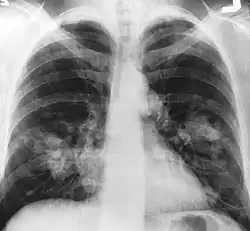

An X-ray scan indicating abnormal masses in the lungs.